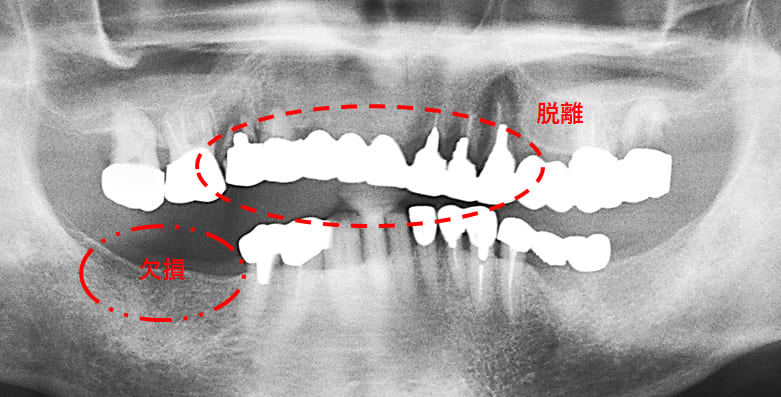

初診時のパノラマXP所見

上顎前歯を含む第2小臼歯から対側の第2小臼歯までの10本のブリッジが脱離しそれを支えていた歯自体が保存できない状態であった。また下顎の臼歯部も欠損しており、このことで垂直的な咬合の安定が得られず前歯に負担がかかる崩壊脱離したと考えられる。

#15,14,21,22,23,27,36が残根状態で温存は不可能であり、患者さん自身もそれを自覚しておられた。